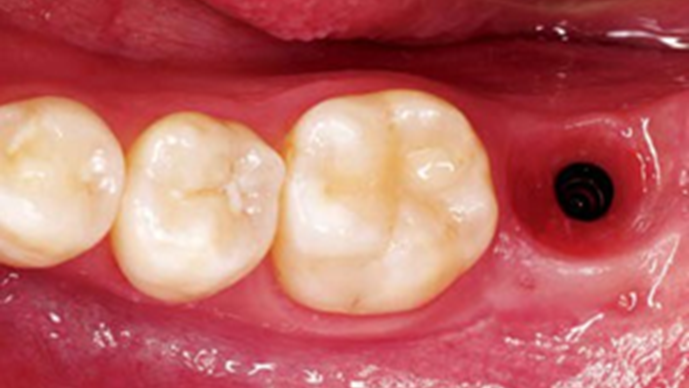

“AnyRidge with Root Membrane Technique shows

comparable long-term success rates to

conventional immediate implants. ”

Clinical case: Replacement of fractured central incisor (#11) with immediate implant

& Root Membrane Technique

- Courtesy of Dr. Miltiadis Mitsias, Greece -

Keywords

AnyRidge, Root Membrane Technique, retrospective study, long-term study, immediate implants, bone resorption, bone preservation, Dr. Miltiadis Mitsias,survival, success, maxillary anterior, single replacement

Products:

AnyRidge implant system, Root Membrane kit

Reference

The Root Membrane Technique: A retrospective clinical study with up to 10 years of follow-up./Implant Dent. 2018 Oct;27(5):564-574

https://www.ncbi.nlm.nih.gov/pubmed/30161062